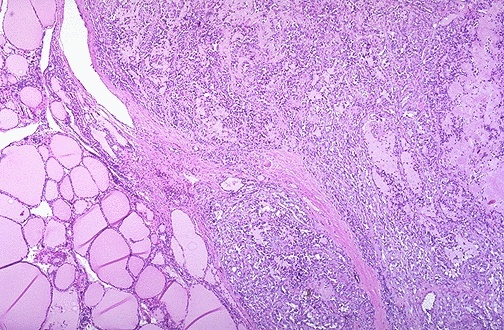

This low power microscopic view of thyroid gland shows an early stage of Hashimoto thyroiditis with prominent lymphoid follicles containing large, active germinal centers. In this autoimmune disease, antithyroglobulin and antimicrosomal (thyroid peroxidase) autoantibodies can often be detected in serum. Other autoimmune diseases such as Addison disease or pernicious anemia may also be present. Both thyroid growth immunoglobulins (TGI) and thyroid stimulating immunoglobulins (TSI) are present, though blocking antibodies to TSI mitigate their effect so that hyperthyroidism is usually not the most prominent features.

This high power microscopic view of the thyroid with Hashimoto’s thyroiditis demonstrates the pink Hürthle cells at the center and right. The lymphoid follicle is at the left. Hashimoto’s thyroiditis initially leads to painless enlargement of the thyroid, followed by atrophy years later.